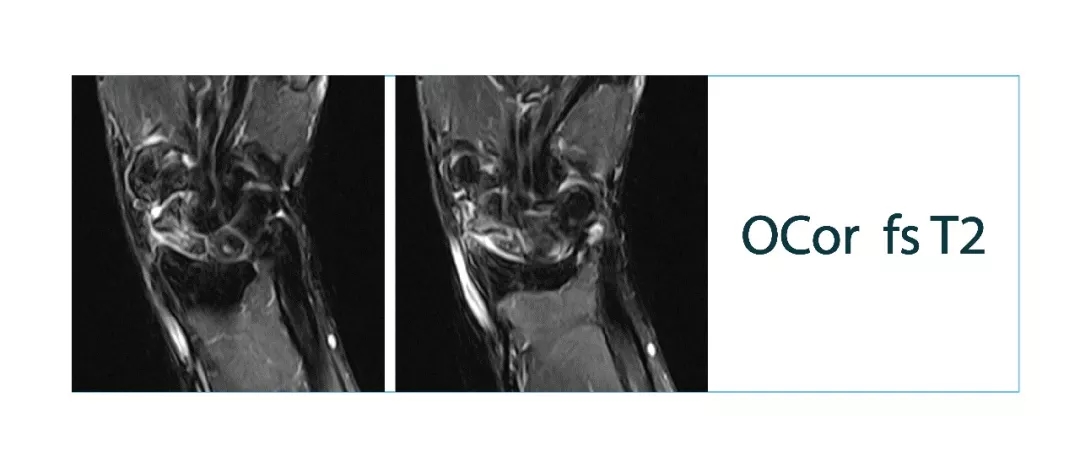

【朗润影像档案】磁共振影像病例分享(编号20180126)